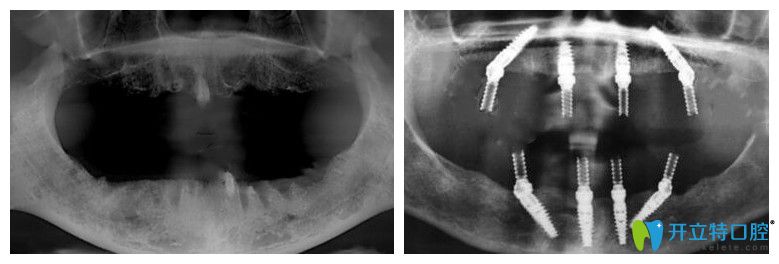

65歲,薛老師;種植前上頜牙齒全部脫落,下頜就剩下四顆殘根;之前戴過(guò)活動(dòng)假牙,但因?yàn)闀r(shí)間長(zhǎng)了戴上很容易掉,所以才考慮做全口種植牙。下面是做種植牙前后的CT片:

薛老師說(shuō)沒(méi)做種植牙前聽(tīng)別人說(shuō)價(jià)格特別貴,但是在靖江艾齒嘉口腔面診、拍片檢查后,陳濤醫(yī)生建議自己做ALL-ON-4全口種植牙,上下頜各植入4顆種植體,就能支撐全口牙冠,這種方法不僅讓自己省了很多錢(qián),而且吃東西的咀嚼力也強(qiáng)。